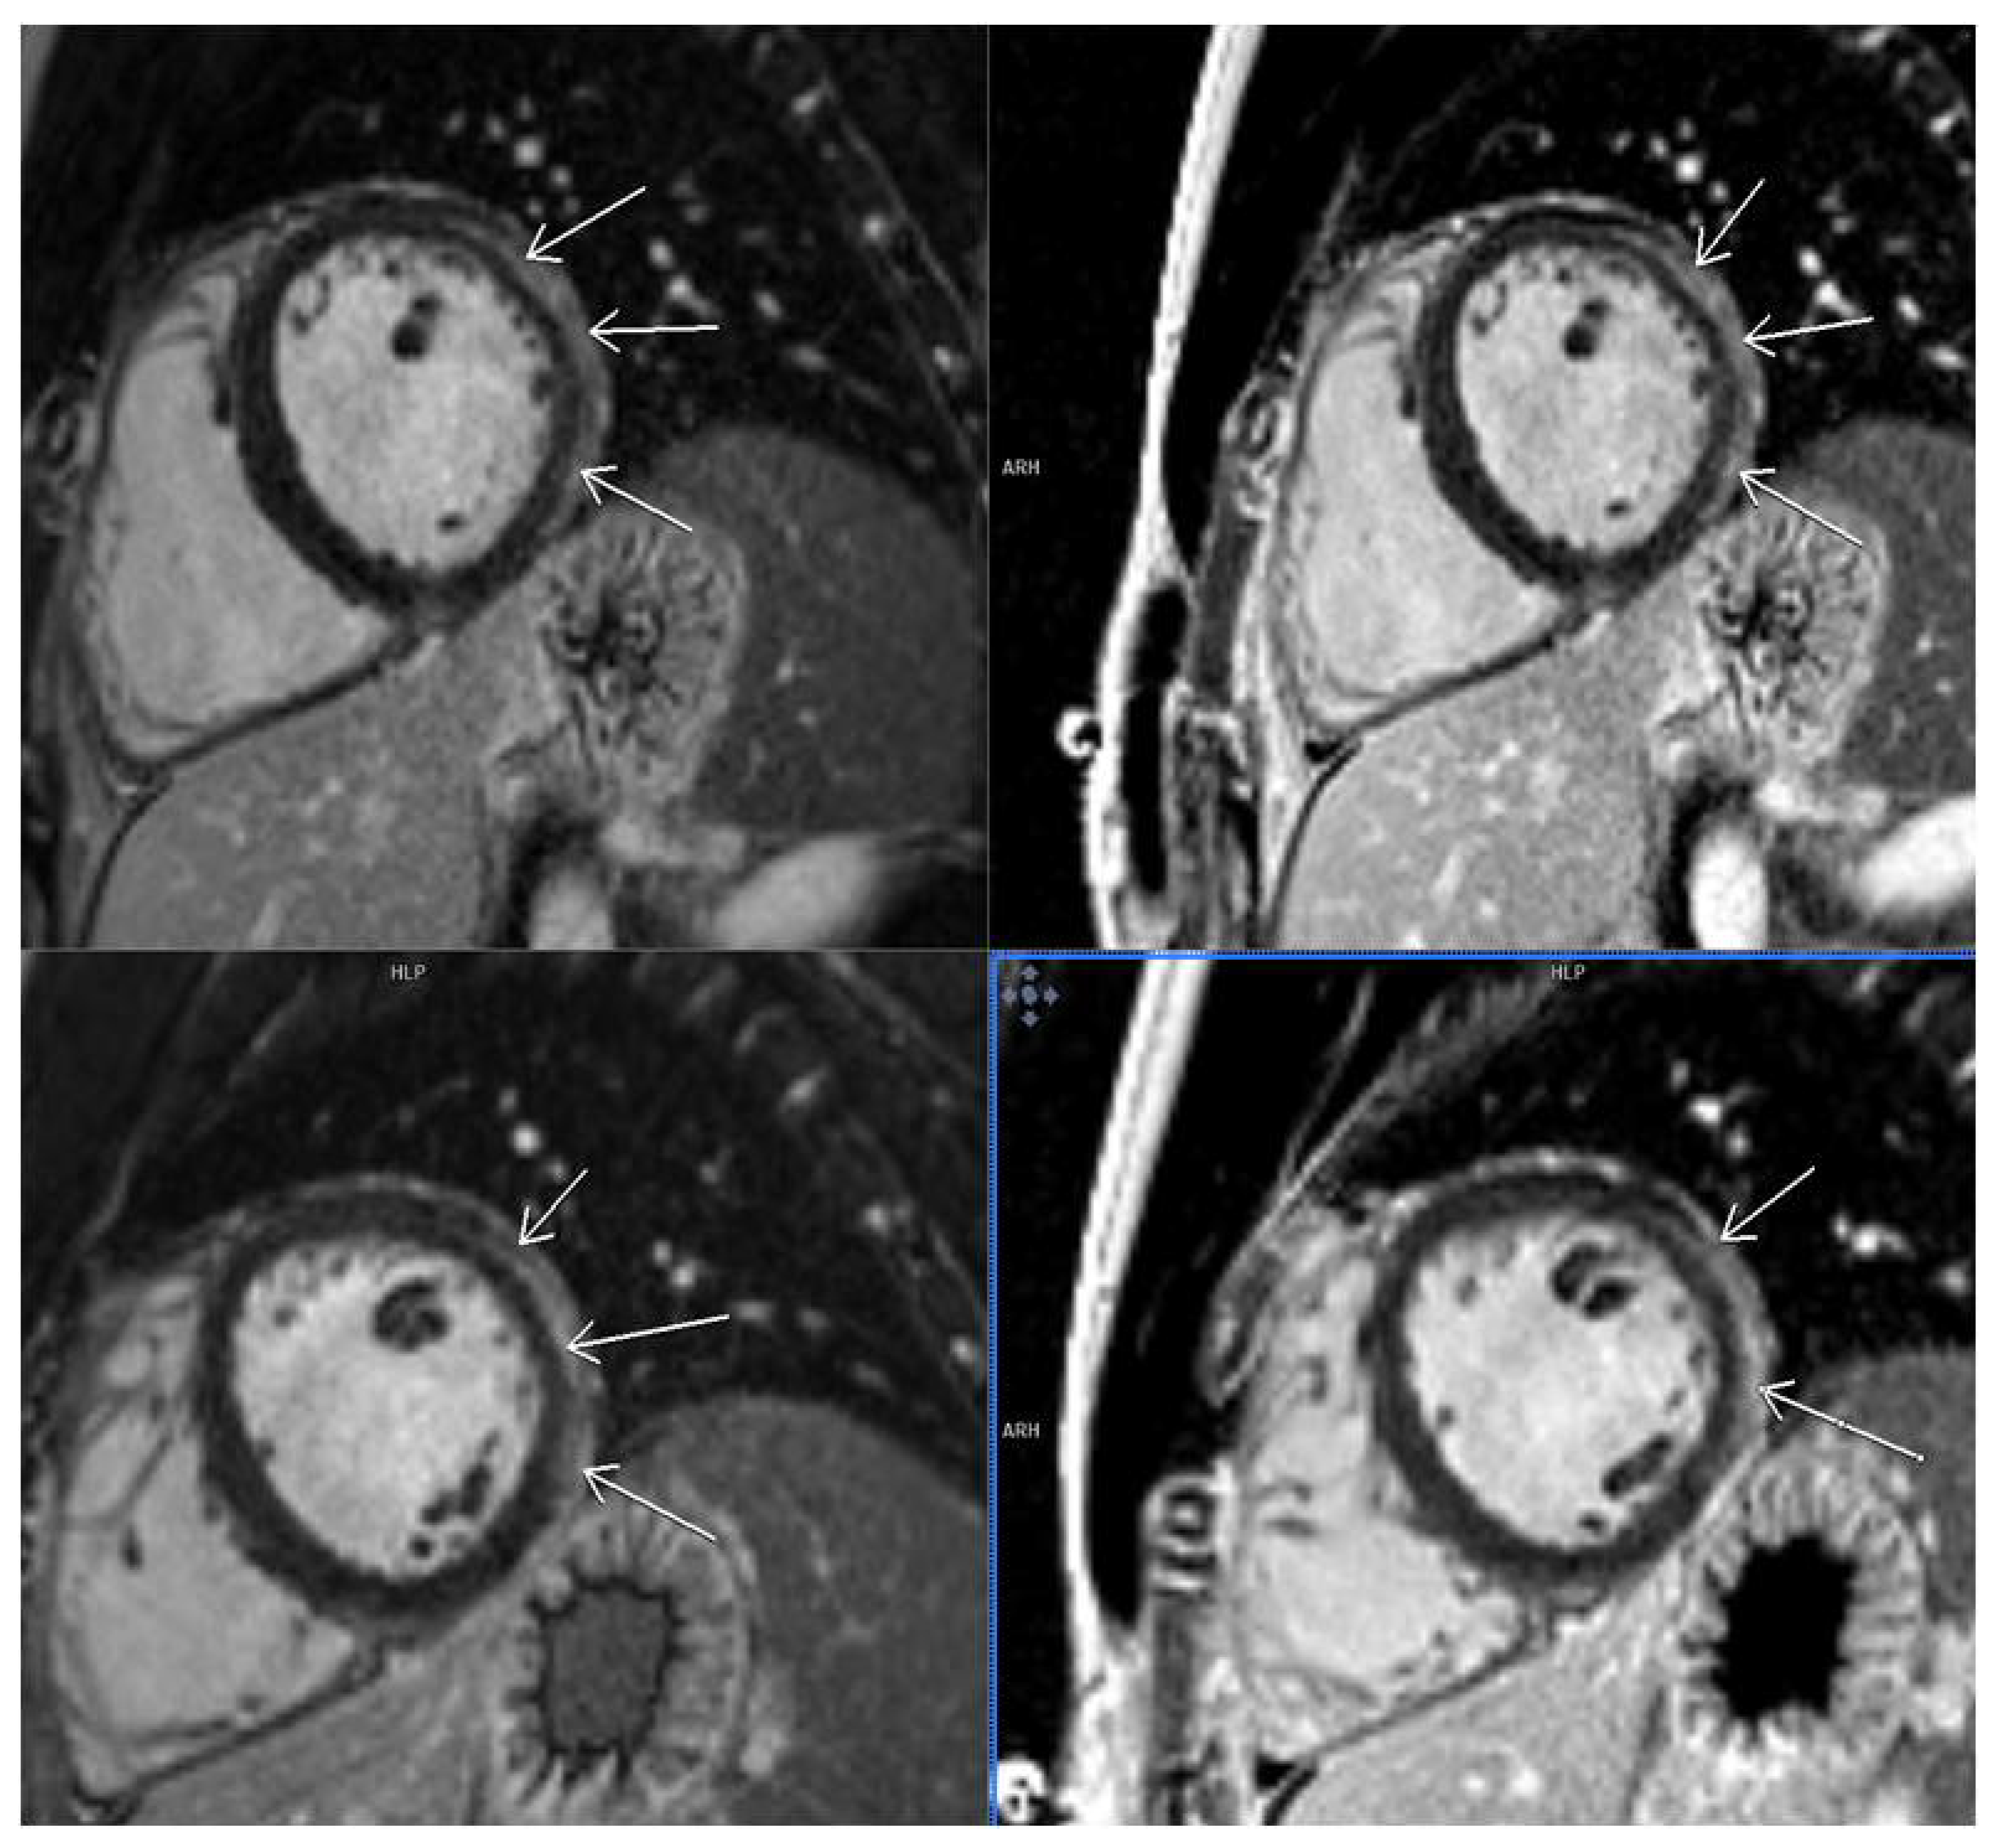

3.2. CMR Findings

3.5. LGE Localization

| T1 mappingvalues | 1063.5 ± 9.7 ms | 1103.9 ± 17.2 ms | p = 0.033 | t = −2.2 | Yes |